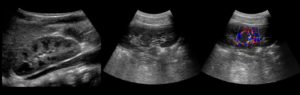

Губчатая почка является аномалией развития – врожденным расширением структурных составляющих – собирательных трубочек. Для большинства пациентов эта аномалия безобидна и протекает без каких-либо клинических проявлений. Но у части людей такая патология способствует развитию восходящей инфекции, требующей соответствующего лечения.

При эхографии пирамидки почки, которые в норме гипоэхогенные (темно-серые), в результате увеличения числа отражающих поверхностей раздела сред за счет расширения трубочек становятся гиперэхогенными (белыми).

С возрастом возможно вторичное обызвествление расширенных собирательных трубочек, а также образование кист в корковом веществе аномального органа. При этом губчатая почка начинает напоминать изменения при нефрокальцинозе, но без сопутствующих изменений в лабораторных анализах.